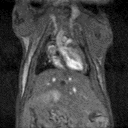

MRI is a complementary method to bioluminescence imaging in the detection of tumors, allowing a more precise assessment of the location and extent of orthotopic tumors (here, an orthotopic model of prostate bone marrow metastasis). Image Credit: Scintica Instrumentation Inc

Alternatively, the animal can be transported to different imaging modalities using a multimodal imaging cassette to fit inside the MRI coil on the M-Series. These images can be co-registered using third-party software like VivoQuant.